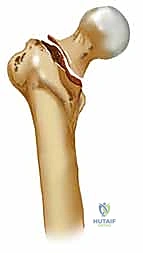

لفهم طبيعة الكسر، يجب أولاً فهم البنية الهندسية والبيولوجية المذهلة لمفصل الورك. يتكون مفصل الورك من التقاء رأس عظم الفخذ الكروي مع التجويف الحقي في الحوض. أسفل عنق الفخذ مباشرة، توجد منطقة بارزة تُعرف بمنطقة المدورين (Trochanteric Region).

المدور الكبير والمدور الصغير

- المدور الكبير (Greater Trochanter): هو بروز عظمي كبير يقع في الجزء الخارجي العلوي من عظم الفخذ. يعمل كنقطة ارتكاز حيوية لارتباط العضلات القوية المسؤولة عن إبعاد الفخذ (Abductors) مثل العضلة الألوية الوسطى والصغرى.

- المدور الصغير (Lesser Trochanter): بروز أصغر يقع في الجزء الداخلي والخلفي، وهو نقطة اتصال العضلة الحرقفية القطنية (Iliopsoas)، وهي العضلة الرئيسية المسؤولة عن ثني الورك.

أهمية موقع الكسر (خارج المحفظة المفصلية)

تُصنف كسور الورك المدورية على أنها "خارج المحفظة المفصلية" (Extracapsular). هذا التمييز التشريحي ليس مجرد مصطلح طبي، بل له دلالات علاجية هائلة. على عكس كسور عنق الفخذ (داخل المحفظة) التي تعاني من ضعف شديد في التروية الدموية مما يهدد بموت رأس العظم (Avascular Necrosis)، تتمتع منطقة المدورين بشبكة دموية غنية جداً. هذا يعني أن العظم المكسور هنا لديه قدرة بيولوجية ممتازة على الالتئام إذا تم تثبيته ميكانيكياً بشكل صحيح.